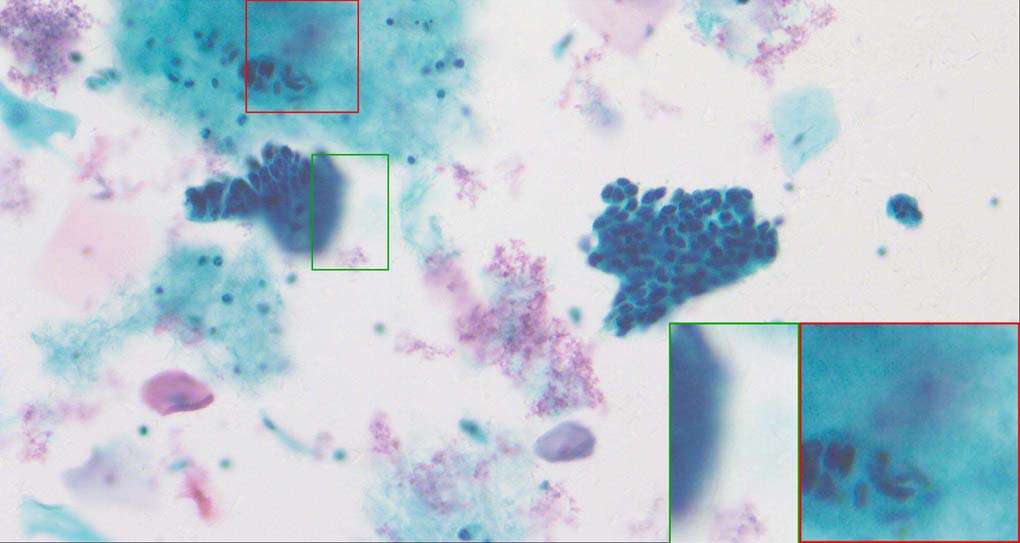

To demonstrate the effectiveness and efficiency of the proposed image fusion method , we conduct a set of comparative experiments on three image datasets. The first is composed by 8 pairs of multi-modal medical images and the second one contains 15 pairs of multi-focus gray or color natural images. These two datasets are often used in many related papers and some examples are shown in Figure 3(a) and Figure 3(b). The third one is a new multi-focus cervical cell image dataset collected by ourselves, which consists of 15 groups of color images and each group contains a series of multi-focus cervix cell images with size of or , etc. Some source examples are shown in Figure 3(c). Our source code implemented in C++ along with the new multi-focus cervical cell image dataset is available online.

Figure 9, Figure 10 and Figure 11 show the comparative fused results of the multi-focus cell images shown in Figure 3(c). For clarity, we also present a closeup view in the right-bottom of each sub-picture in Figure 9 and Figure 10. As shown in the close-up views of Figure 9, the fused images based on DSIFT, IM, MWGF and BF methods are extremely blurred in the boundary and fail to keep the details of cell nucleus. Furthermore, the DTCWT and NSCT based methods produce halo artifacts in the fused images, while GFF and CNN based methods fail to preserve the small cell nucleus. LP-SR based method nearly works fine which keeps the most of the details of the small size cells, but the integrity of the clustered large size cells is damaged. Fortunately, in our proposed method, the integrity of the clustered large size cells is preserved and most of the isolated small size cells are maintained from the original images, which demonstrates the best visual quality.

Similarly, as shown in the close-up views of Figure 10, the fused images from DSIFT, IM, MWGF and BF are blurred and lose some nucleus details, while the results from DTCWT, GFF, CNN and NSCT produce halo artifacts. LP-SR based method can keep details well but also produces halo artifacts and other noise. Our method can preserve the focused areas of different source images well without introducing any artifacts. For the example illustrated in Figure 11, the fused images generated by DSIFT, DTCWT, IM and NSCT all fail to preserve the focused areas of different source images and result in extremely blurred images. The GFF, CNN, MWGF and BF based method introduces a lot of color distortion of the nucleus regions and the obvious halo artifact. The result of LP-SR based method is close to the one of our method but introduces some odd color distortion. Again, our method produces fused image which can preserve the focused areas of different source images well without introducing any artifacts.